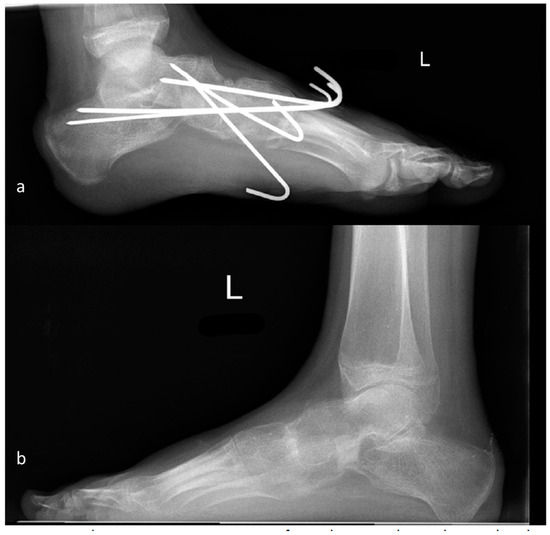

2.1. Operative Procedure

2.2. Clubfoot

2.3. Pes Cavovarus

2.4. Pes Planovalgus

2.4.4. Triple Fusion